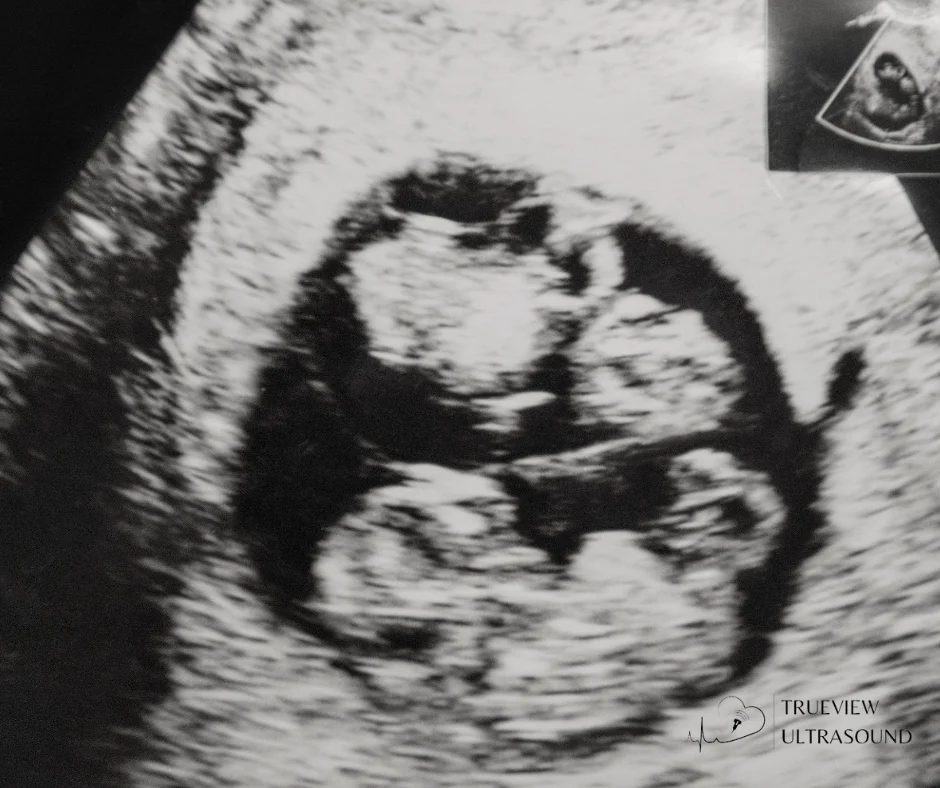

- 3D Ultrasound – Provides three-dimensional still images, offering expectant parents a glimpse of their baby’s features.

- 4D Ultrasound – Captures real-time movements, showcasing the baby’s expressions.

- 5D Ultrasound – Utilizes advanced light rendering for a near-photorealistic image of the fetus.

For expectant parents looking for detailed, high-quality fetal imaging, our advanced fetal imaging services provide an unforgettable bonding experience.